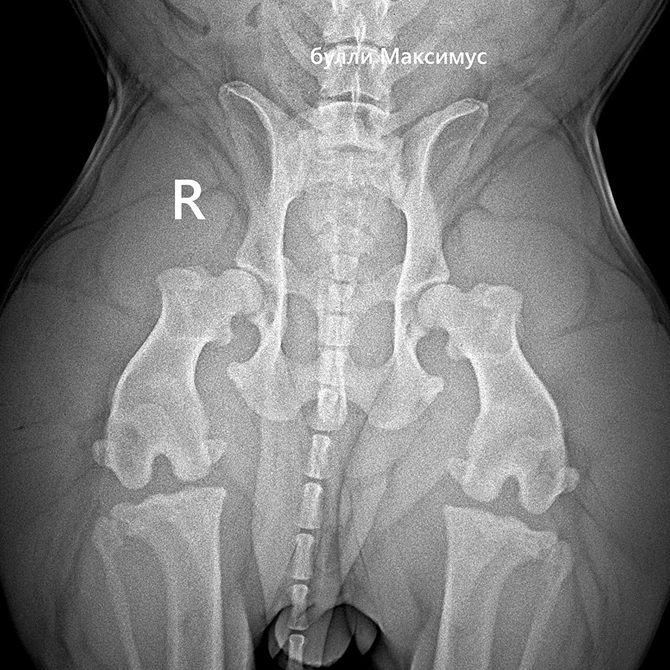

- эхокардиограмму сердца,

- осмотр ортопеда,

- УЗИ всех органов,

- вакцинации, чипирование, купирование ушей и обработки.